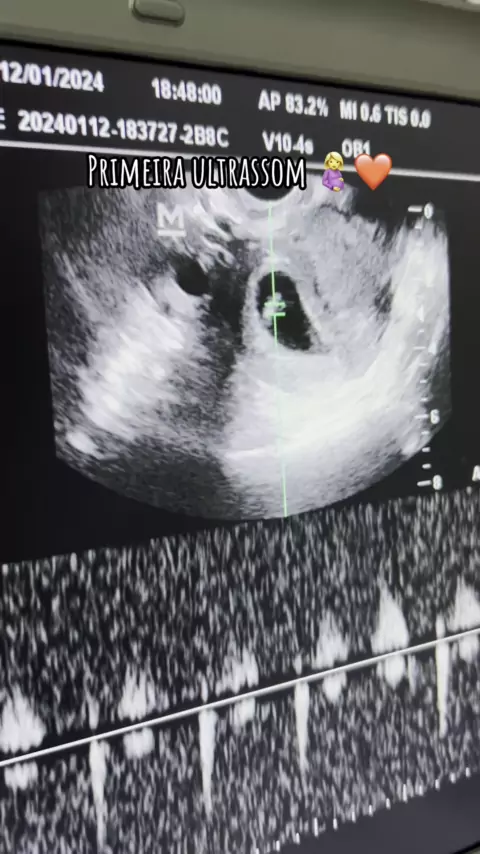

O som mais lindo que já ouvi. ❤️🥹 #gravidez #gestaçao #ultra #baby